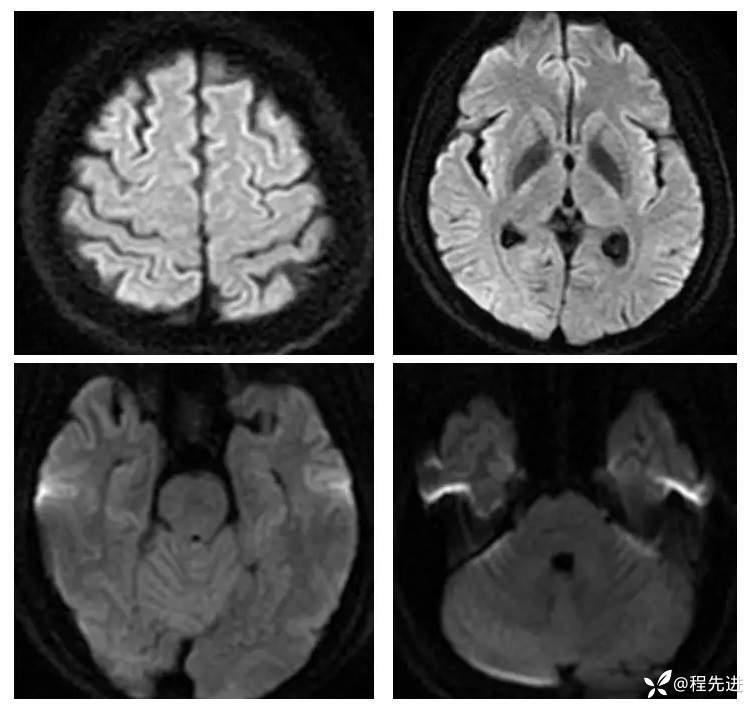

【现病史及既往史】:孕期38周,蛋白尿10天,血压升高6天,剖腹产后一天出现头晕,头痛,嗜睡。既往糖尿病史

查体:不配合,血压波动,130-157/85-109mmHg

影像检查: